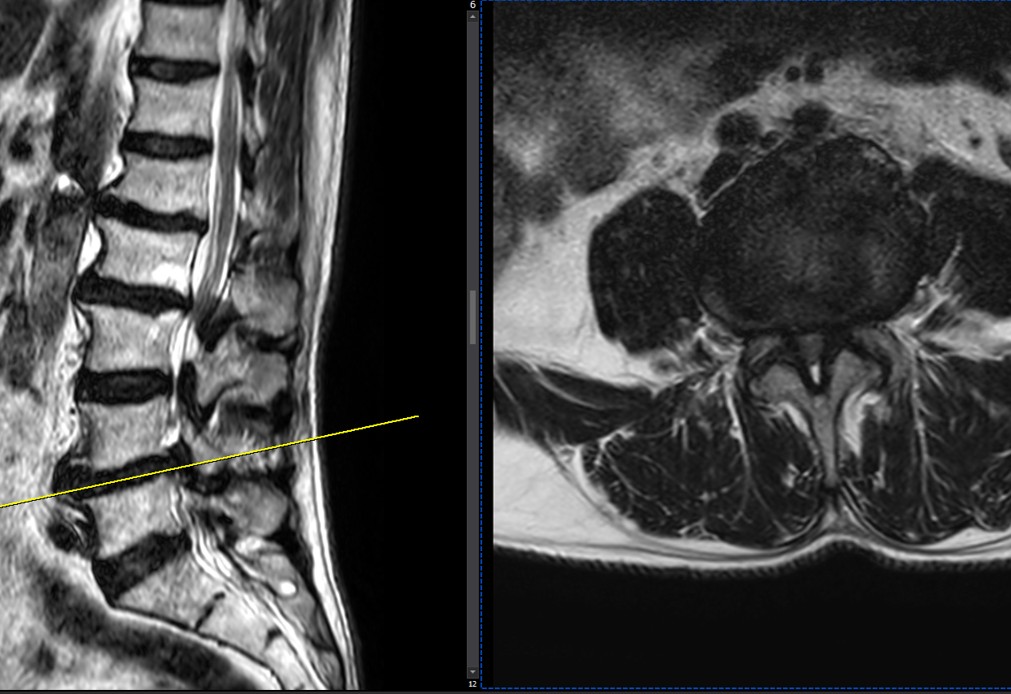

41 years old man presented to my clinic in October 2023 with acute and sever R neck pain with radicular pain to his R upper extremity along C6 dematom since 2 weeks ago. Examination didn’t show any upper motor signs. Was suggested urgent surgery

I ordered EMG/ NCV : showed mild R C6, C7 irritation without any active axonal loss

In his MRI was reported R. para R. IVF Massive extrusion. I decided to control his pain and manage this patient with reevaluation of patient every other session. For 5 sessions i just used acupuncture and laser and IFC and mild adjustments to his R. T3-T7 and mild arthosteem to above and below involved segment. Cervical adjustment considered contraindicated for this patient. From session 6th- 8th i started to use mild/gentle cervical decompression. He used soft cervical collar all the time. His pain decreased by 80 percent

I gave him cervical traction pump to be used 3-5 times per day at home for the next 3 months and i released the patient. He was evaluated every week once for one month and after that every 2 weeks. After 3 month I repeated MRI. Size of the herniated disc was reduced greater than 50 percent. Asked him to do another mri in 6 months

In general: Precise selection of the patients, examination,diagnosis, plan of management, reevaluation and treatment can be done by doctors of chiropractic for the patients with spinal disc herniation and stenosis Moreover giving reasonable time to these kind of patients under direct supervision by their chiropractic doctors can prevent unnecessary surgery. Proper selection of these kind of patients is another important fact that can be done precisely by chiropractors.

MRIs before and after proper management of this patient: